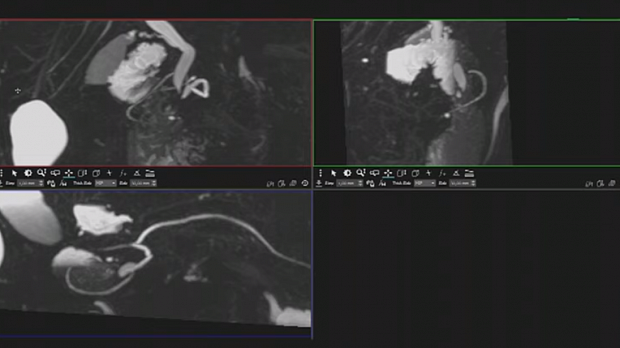

Ответ: кольцевидная поджелудочная железа - "circular pancreas" - это эмбриологический порок развития, характеризующийся наличием кольца ткани поджелудочной железы, полностью или частично окружающего нисходящую (D2 вторую часть) двенадцатиперстной кишки. Его основным клиническим симптомом является полная или частичная дуоденальная непроходимость.

Чаще кольцевидная ПЖ представляет собой неопасный вид аномального развития железы, который или не причиняет особых беспокойств больному, или при достаточно выраженном стенозе, относительно просто корригируется оперативным пособием. В то же время кольцевидная ПЖ примерно в 30 % случаев сочетается с другими аномалиями развития органов желудочно-кишечного тракта, а в ряде случаев — других органов и систем. Эта аномалия может быть частью сложных комбинированных дефектов развития, в том числе и не совместимых с жизнью. Если рассматривать более часто встречающиеся случаи, когда pancreas annulare является изолированным пороком развития, то ее клинические проявления во многом определяются степенью сдавления двенадцатиперстной кишки и нарушением ее проходимости.

Иллюстрация №1: GGG